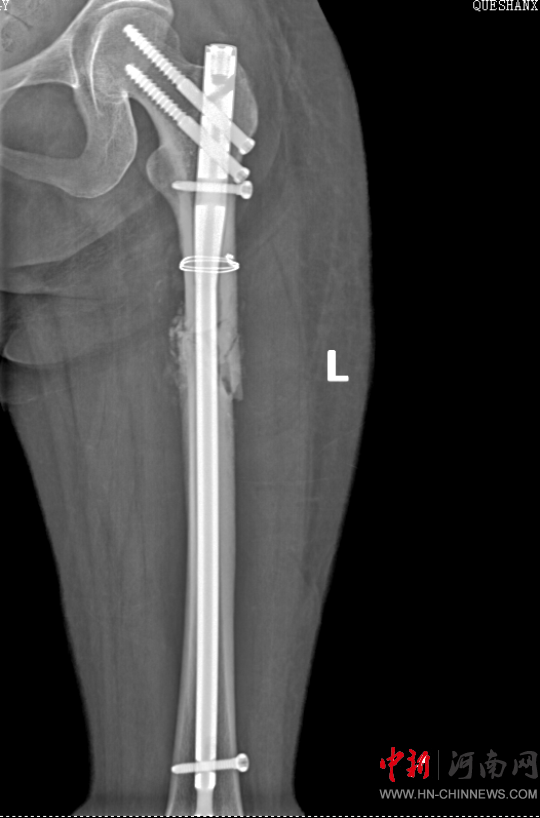

患者病情好轉(zhuǎn)后,該院急診科主任岳春彥和創(chuàng)傷治療團(tuán)隊(duì)為患者制定了詳細(xì)的手術(shù)規(guī)劃,傷后第10日,患者在全身麻醉下進(jìn)行“左股骨粉碎骨折及脛骨粉碎骨折髓內(nèi)釘內(nèi)固定術(shù)+骨移植術(shù)、腓骨骨折復(fù)位內(nèi)固定術(shù)”,病情平穩(wěn)后轉(zhuǎn)入急診科病房治療,切口愈合后,患者轉(zhuǎn)入康復(fù)醫(yī)學(xué)科進(jìn)行腦功能康復(fù)和下肢關(guān)節(jié)康復(fù)治療。目前,患者能夠與人正常溝通交流,左下肢關(guān)節(jié)功能也恢復(fù)良好,已出院。